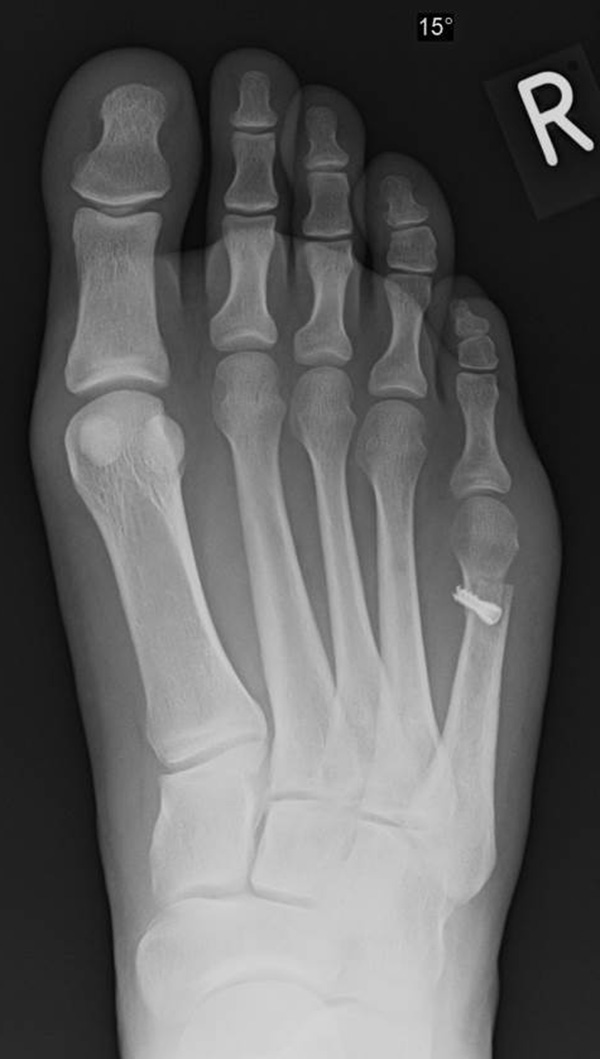

Abb. 3a, b: Präoperatives (a) und postoperatives (b) Röntgenbild bei Korrektur einer Typ I Deformität durch eine Exostosenabtragung.